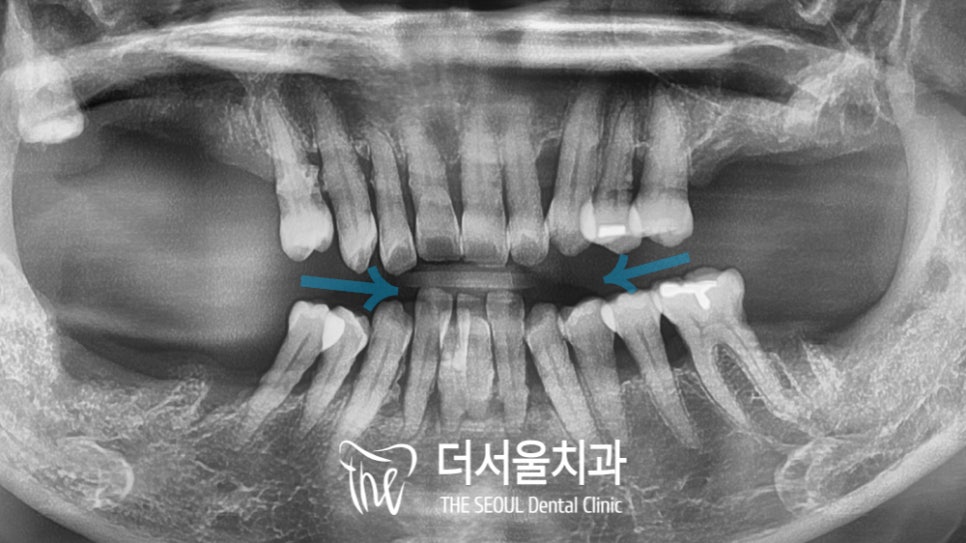

파노라마 사진을 살펴보니

구치부 치아들은 이미 상실되어 있었으며

남아있던 곳들도 치조골 소실이

심하게 나타나 있는 것은 물론,

전체적으로 근심 방향으로 쏠려 있었는데요.

살릴 수 있는 치아들이

몇 되지 않은 것으로 확인이 되었습니다.

특히 앞니 주변으로 큰 흔들림을

느끼고 있었기 때문에 치료가 급해 보였죠.